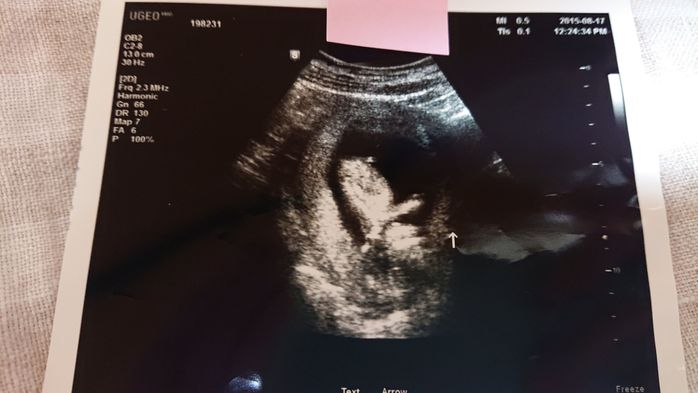

《妊娠7週目のエコー写真》

妊娠7週目の健診日には、午前中に夫と一緒に市役所へ婚姻届けを提出し、母子手帳も発行してもらいました。夫は車酔いをして具合が悪くなってしまったので、健診の時は夫には留守番をしてもらい、もらいたてホヤホヤの母子手帳を手に、1人でドキドキしながら産婦人科へ行きました。すると、胎嚢の中に赤ちゃんの姿が…!「やっと会えたね~」と、嬉しすぎて食い入るように見ていたエコーの画面。「もっともっと長く見ていたい」と切に願ったほど感激しました。そして、この日は同時に心拍も確認でき、心臓も元気に動いていました。2枚目のエコー写真の右側半分が、心拍を確認できた証拠です。医師からは「小さすぎて予定日はまだ決められないな~。でも、3月上旬ぐらいになるかな~」と伝えられ、予定日確定は次回持ち越しに。夫は「成長遅いんじゃない?」と心配そうにしていました。翌日には、私たちの結婚式が控えていました。その前に赤ちゃんの姿を見つけることができたおかげで、遠方の両親にも直接妊娠報告することができて嬉しかったです。